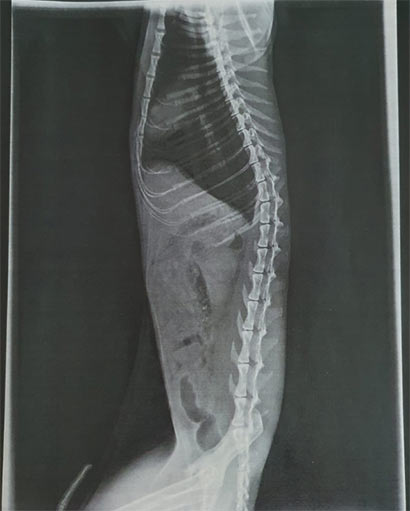

Leider kann der Kater seine Hinterbeine nicht mehr bewegen, aber die Prognosen stehen nicht ganz so schlecht, da die Röntgenbilder keine Schädigung der Wirbelsäule zeigt und er auch noch selbständig Urin und Kot absetzen kann.